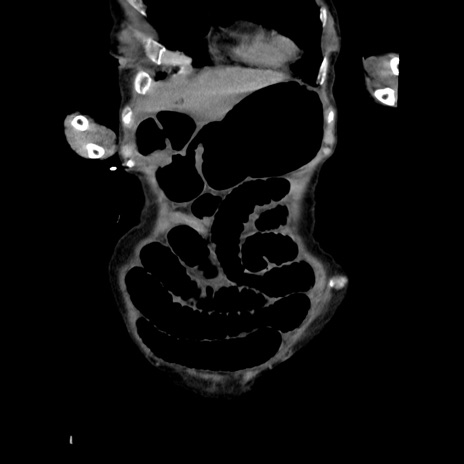

症例27(冠状断像)

【症例】80歳代女性

【主訴】嘔吐、腹痛

【現病歴】数時間前より嘔吐あり。心窩部痛出現し、徐々に右下腹痛あり。その後も数回嘔吐あり救急搬送となる。

【既往歴】左大腿骨頚部骨折手術

【身体所見】腹部は膨隆しているが軟らかく圧痛なし。腸雑音はやや亢進。

【データ】WBC 12000、CRP 19.05